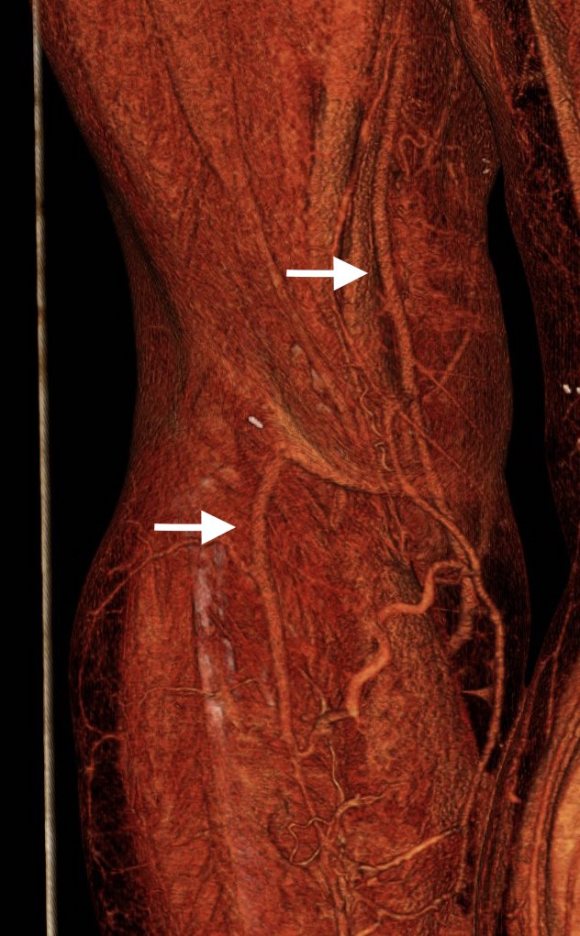

On examination, he had heavy scarring in both groins from prior open incisions healed by secondary intention, a midline laparotomy incision. He had weak bilateral axillary and brachial artery pulses. He had no pulses in either leg. The right foot had gangrene of the distal phalanx of the third toe. The both feet were anemic and painful -the left foot had more dependent rubor. Pulse volume recordings were flat in both legs. TCPO2 was in the 20-40mmHg range at the thighs bilaterally suggesting reduced potential for healing an above knee amputation. Vein mapping showed no suitable saphenous vein in either leg. CTA (figure below) showed both external iliac arteries to be occluded or absent and the common femoral arteries to be occluded or missing bilaterally.

The left femoral bifurcation was preserved and the left SFA was patent into small underfilled tibial vessels. On the right, there was an isolated segment of profunda femoral artery that reconstituted from pelvic collaterals. The right below knee popliteal artery reconstituted and had underfilled but patent three vessel runoff (figure below).